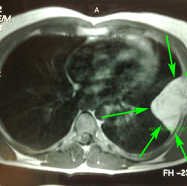

Preop CT. Green: atypical lipomatous tumour of the 5th left rib

Preop MRI. Green arrows: tumour